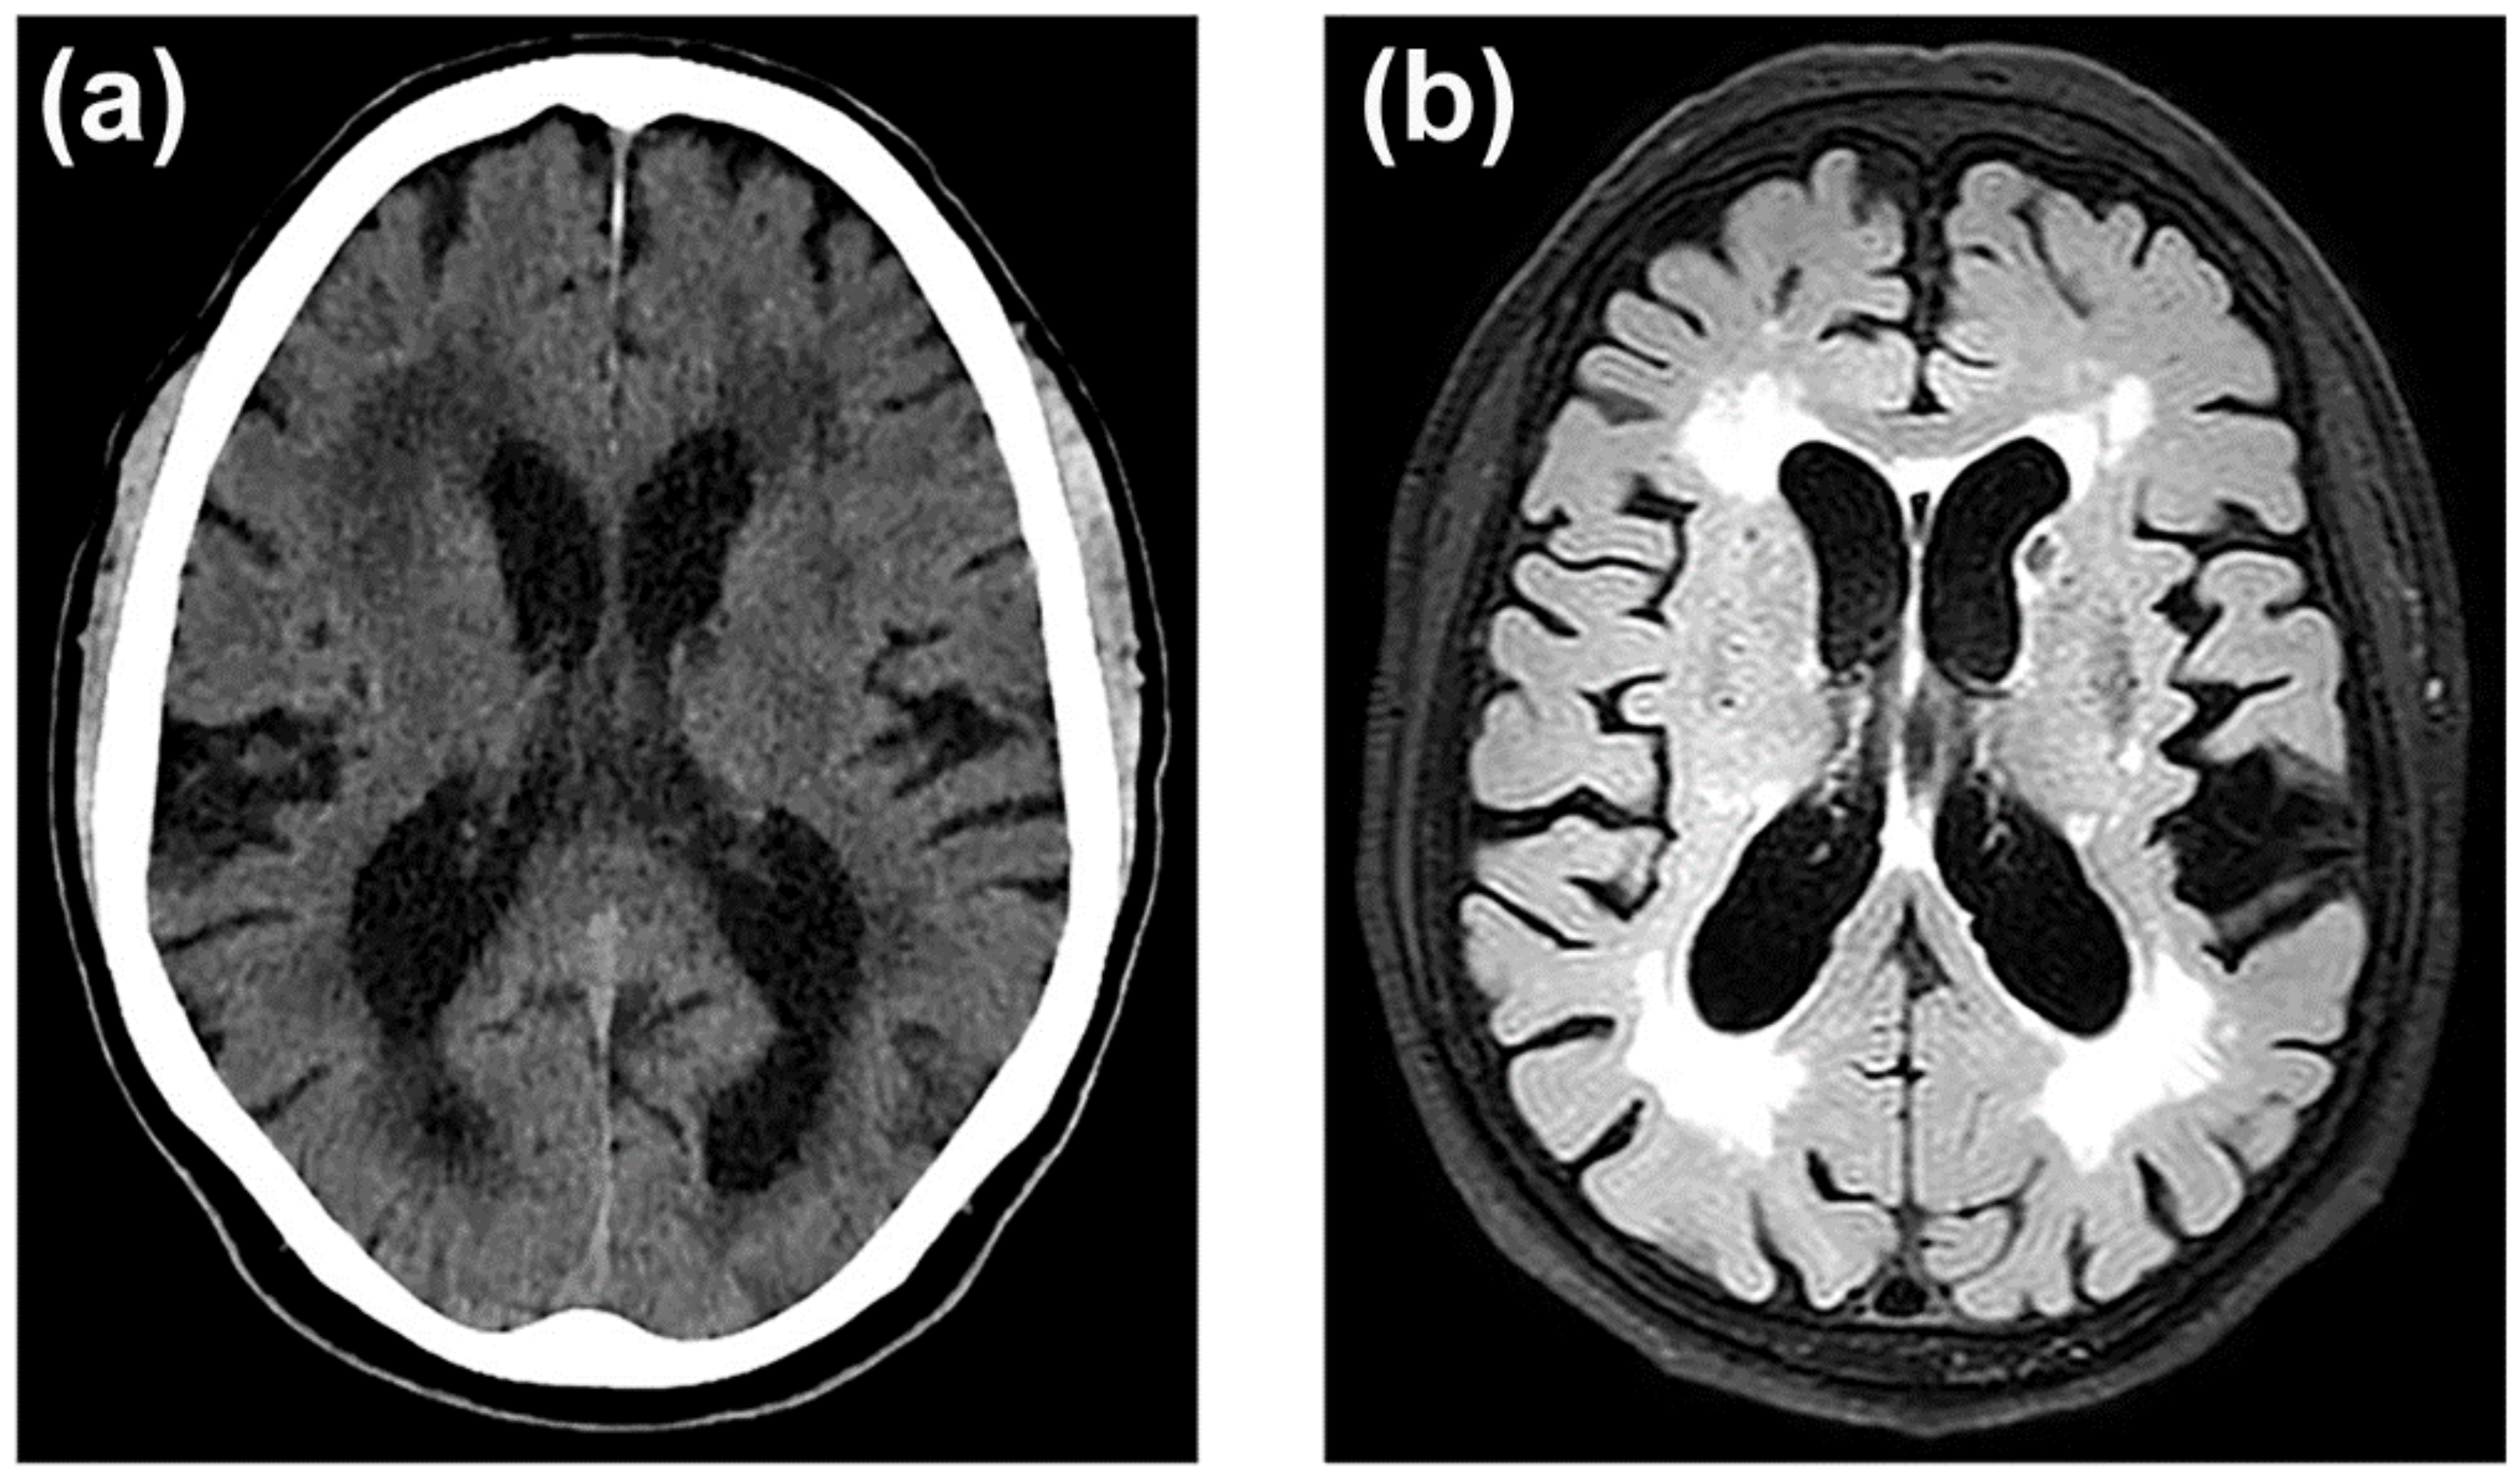

3.7. Neuroimaging of BBB Dysfunction

- Hachinski, V.C.; Potter, P.; Merskey, H. Leuko-Araiosis. Arch. Neurol. 1987, 44, 21–23. [Google Scholar] [CrossRef]

- Wardlaw, J.M.; Smith, E.E.; Biessels, G.J.; Cordonnier, C.; Fazekas, F.; Frayne, R.; Lindley, R.I.; O’Brien, J.T.; Barkhof, F.; Benavente, O.R.; et al. Neuroimaging Standards for Research into Small Vessel Disease and Its Contribution to Ageing and Neurodegeneration. Lancet Neurol. 2013, 12, 822–838. [Google Scholar] [CrossRef]

- Ferguson, K.J.; Cvoro, V.; MacLullich, A.M.J.; Shenkin, S.D.; Sandercock, P.A.G.; Sakka, E.; Wardlaw, J.M. Visual Rating Scales of White Matter Hyperintensities and Atrophy: Comparison of Computed Tomography and Magnetic Resonance Imaging. J. Stroke Cerebrovasc. Dis. 2018, 27, 1815–1821. [Google Scholar] [CrossRef]